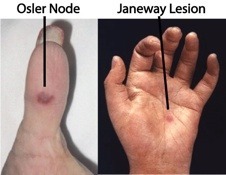

- Nódulos de Osler ☤.

- Lesión de Janeway ☤.